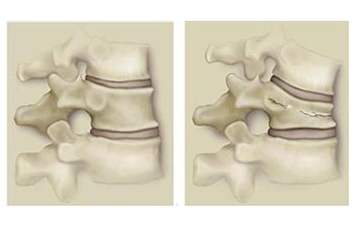

腰椎间盘是椎骨之间坚韧的盘状组织,外围是纤维环,包围在中间是果冻样的髓核。腰椎间盘可以起到缓冲以及协助脊柱活动的作用。在反复扭转腰背部的应力作用下,纤维环可能出现损伤、破裂,从而造成髓核的向外移位,这种移位由轻到重为:膨出—突出—脱出,突出的椎间盘可以通过直接压迫以及炎症刺激附近的神经,出现神经痛。

图示正常腰椎间盘以及突出